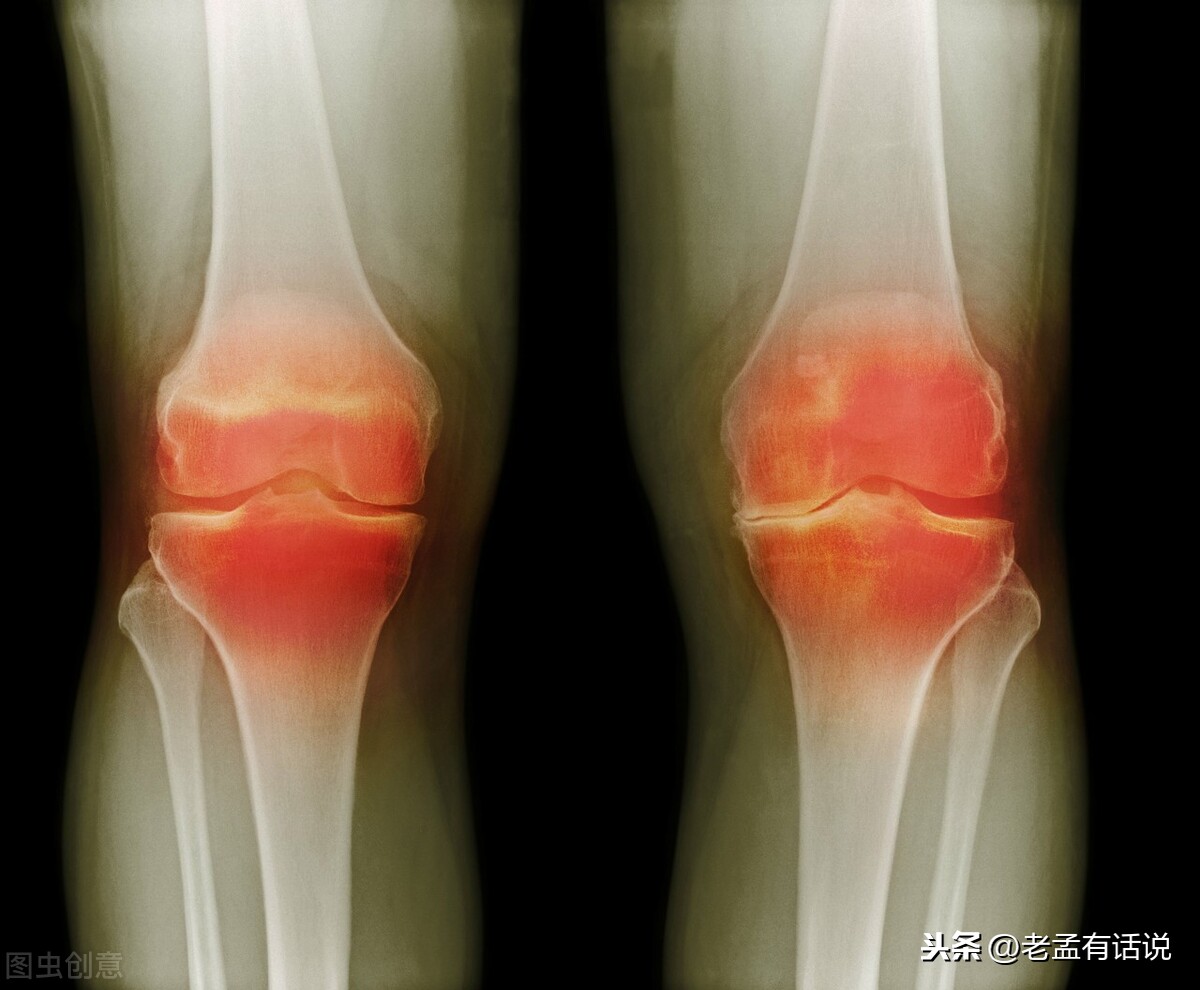

最近由于天气寒冷许多膝关节疼痛的患者来门诊就诊。那么冬季为什么是膝关节关节炎症状加重的一个季节呢?今天给大家科普一下。

第一,在自然状态下我们膝关节本身的血流就比较缓慢。血液供应不是特别丰富,当受到寒冷刺激的时候会使膝关节周围的血管出现萎缩血供应不足,这个时候呢也会引起我们膝关节的疼痛。第二,当血供应不足的时候,膝关节周围的代谢产物以及炎症因子会堆积在膝关节周围。这个时候我们活动膝关节的时候也会引起疼痛。第三,当血流不畅的时候,我们膝关节周围的肌肉他的收缩力下降,膝关节周围的韧带的弹性会下降,肌肉和韧带对膝关节的稳定性不足。